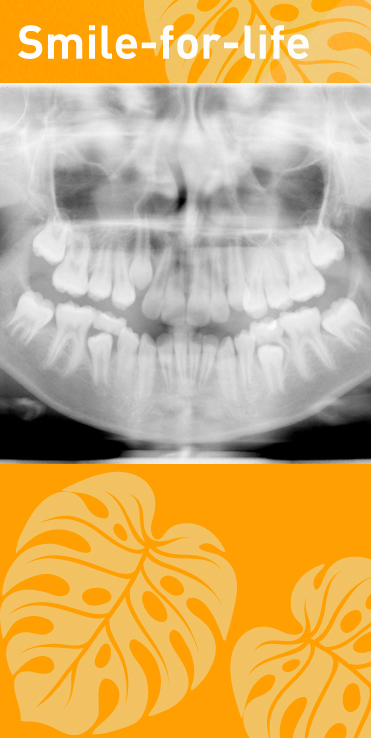

Lückenschluss (statt Implantat)

6er Extraktion (Entfernung der großen Backenzähne) = nach kieferorthopädischen Lückenschluss in unserer Smile-for-life Praxis weist die[...]